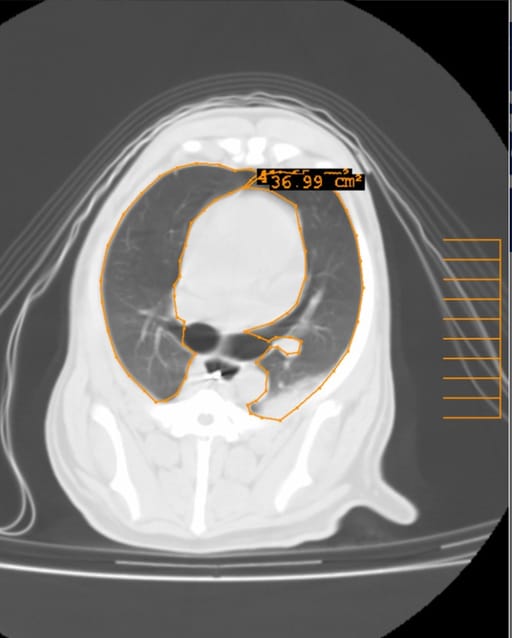

Representative transverse computed tomography image of the thorax of a dog during breath-hold at 5 cmH2O (PP5 group) under general anesthesia. The boundaries of the regions of interest (ROIs) are drawn manually (orange line) on each image. Atelectatic (nonaerated) regions in the dependent lung fields can be detected. The numbers indicate the surface area of the ROIs.

This randomized controlled trial included 60 dogs undergoing thoracic CT for pulmonary metastasis screening. Dogs were assigned to six groups with different PP levels during breath-hold: 0 (control), 5, 8, 10, 12, and 15 cmH₂O. Lung aeration was assessed by analyzing CT images, classifying lung regions as atelectatic, poorly aerated, normally aerated, or hyperinflated. Statistical analyses were performed to compare lung aeration across groups and determine the optimal PP level.

PP levels of 10 and 12 cmH₂O significantly reduced atelectatic and poorly aerated lung regions compared to the control group while increasing normally aerated lung regions. A PP of 15 cmH₂O resulted in mild hyperinflation. No significant differences in heart rate, oxygen saturation, or mean arterial pressure were observed across groups, suggesting that PP levels up to 12 cmH₂O did not cause adverse hemodynamic effects.